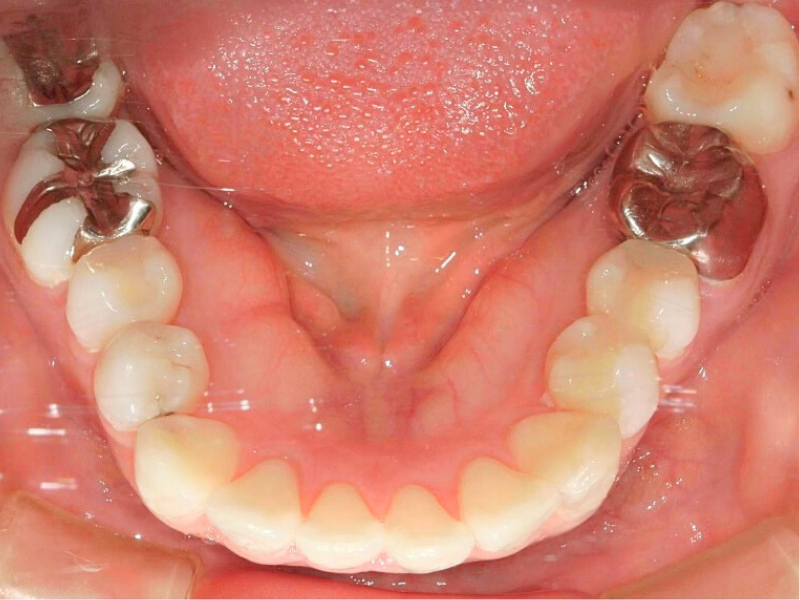

20代、男性、ワイヤー

| 施術内容 | 主訴:でこぼこで食べ物がよく挟まる。虫歯や歯肉炎に悩まされてきた。 詳細:ワイヤー矯正での歯並び改善 とても磨きやすくなったと満足されてます。 |

| 治療期間 | 16ヶ月(2/3現在 治療終了) |

| リスク・副作用 | ■リスク・副作用 ・治療の初期段階では、痛みや不快感が生じやすくなりますが、一週間前後で慣れます。 ・歯の動き方には個人差があるため、予想された治療期間より延長する場合があります。 |

| 費用 | ワイヤー矯正 60万円(税込660,000円) |